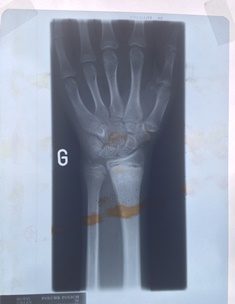

1.Scaphoid

2. Lunate

X-rays are a form of electromagnetic radiation which are emitted when a tungsten target is bombarded with fast electrons in a vacuum tube. They have an extremely short wavelength which means that they can pass through most substances, including human soft tissue, casting shadows of solid objects in their path, such as metal and bone.

The news of Roentgen’s discovery spread quickly throughout the world. One of his first experiments late in 1895 was a film, or shadowgraph, of his wife Bertha’s hand with a ring on her finger. Of all the first pictures of his that were circulated it was that of the human hand that made the greatest impression upon the public. Everywhere people began testing the new radiation by taking pictures of the bones in their hands.

Human hands contain 27 bones.

Among them, the lunate, the scaphoid, the capitate.